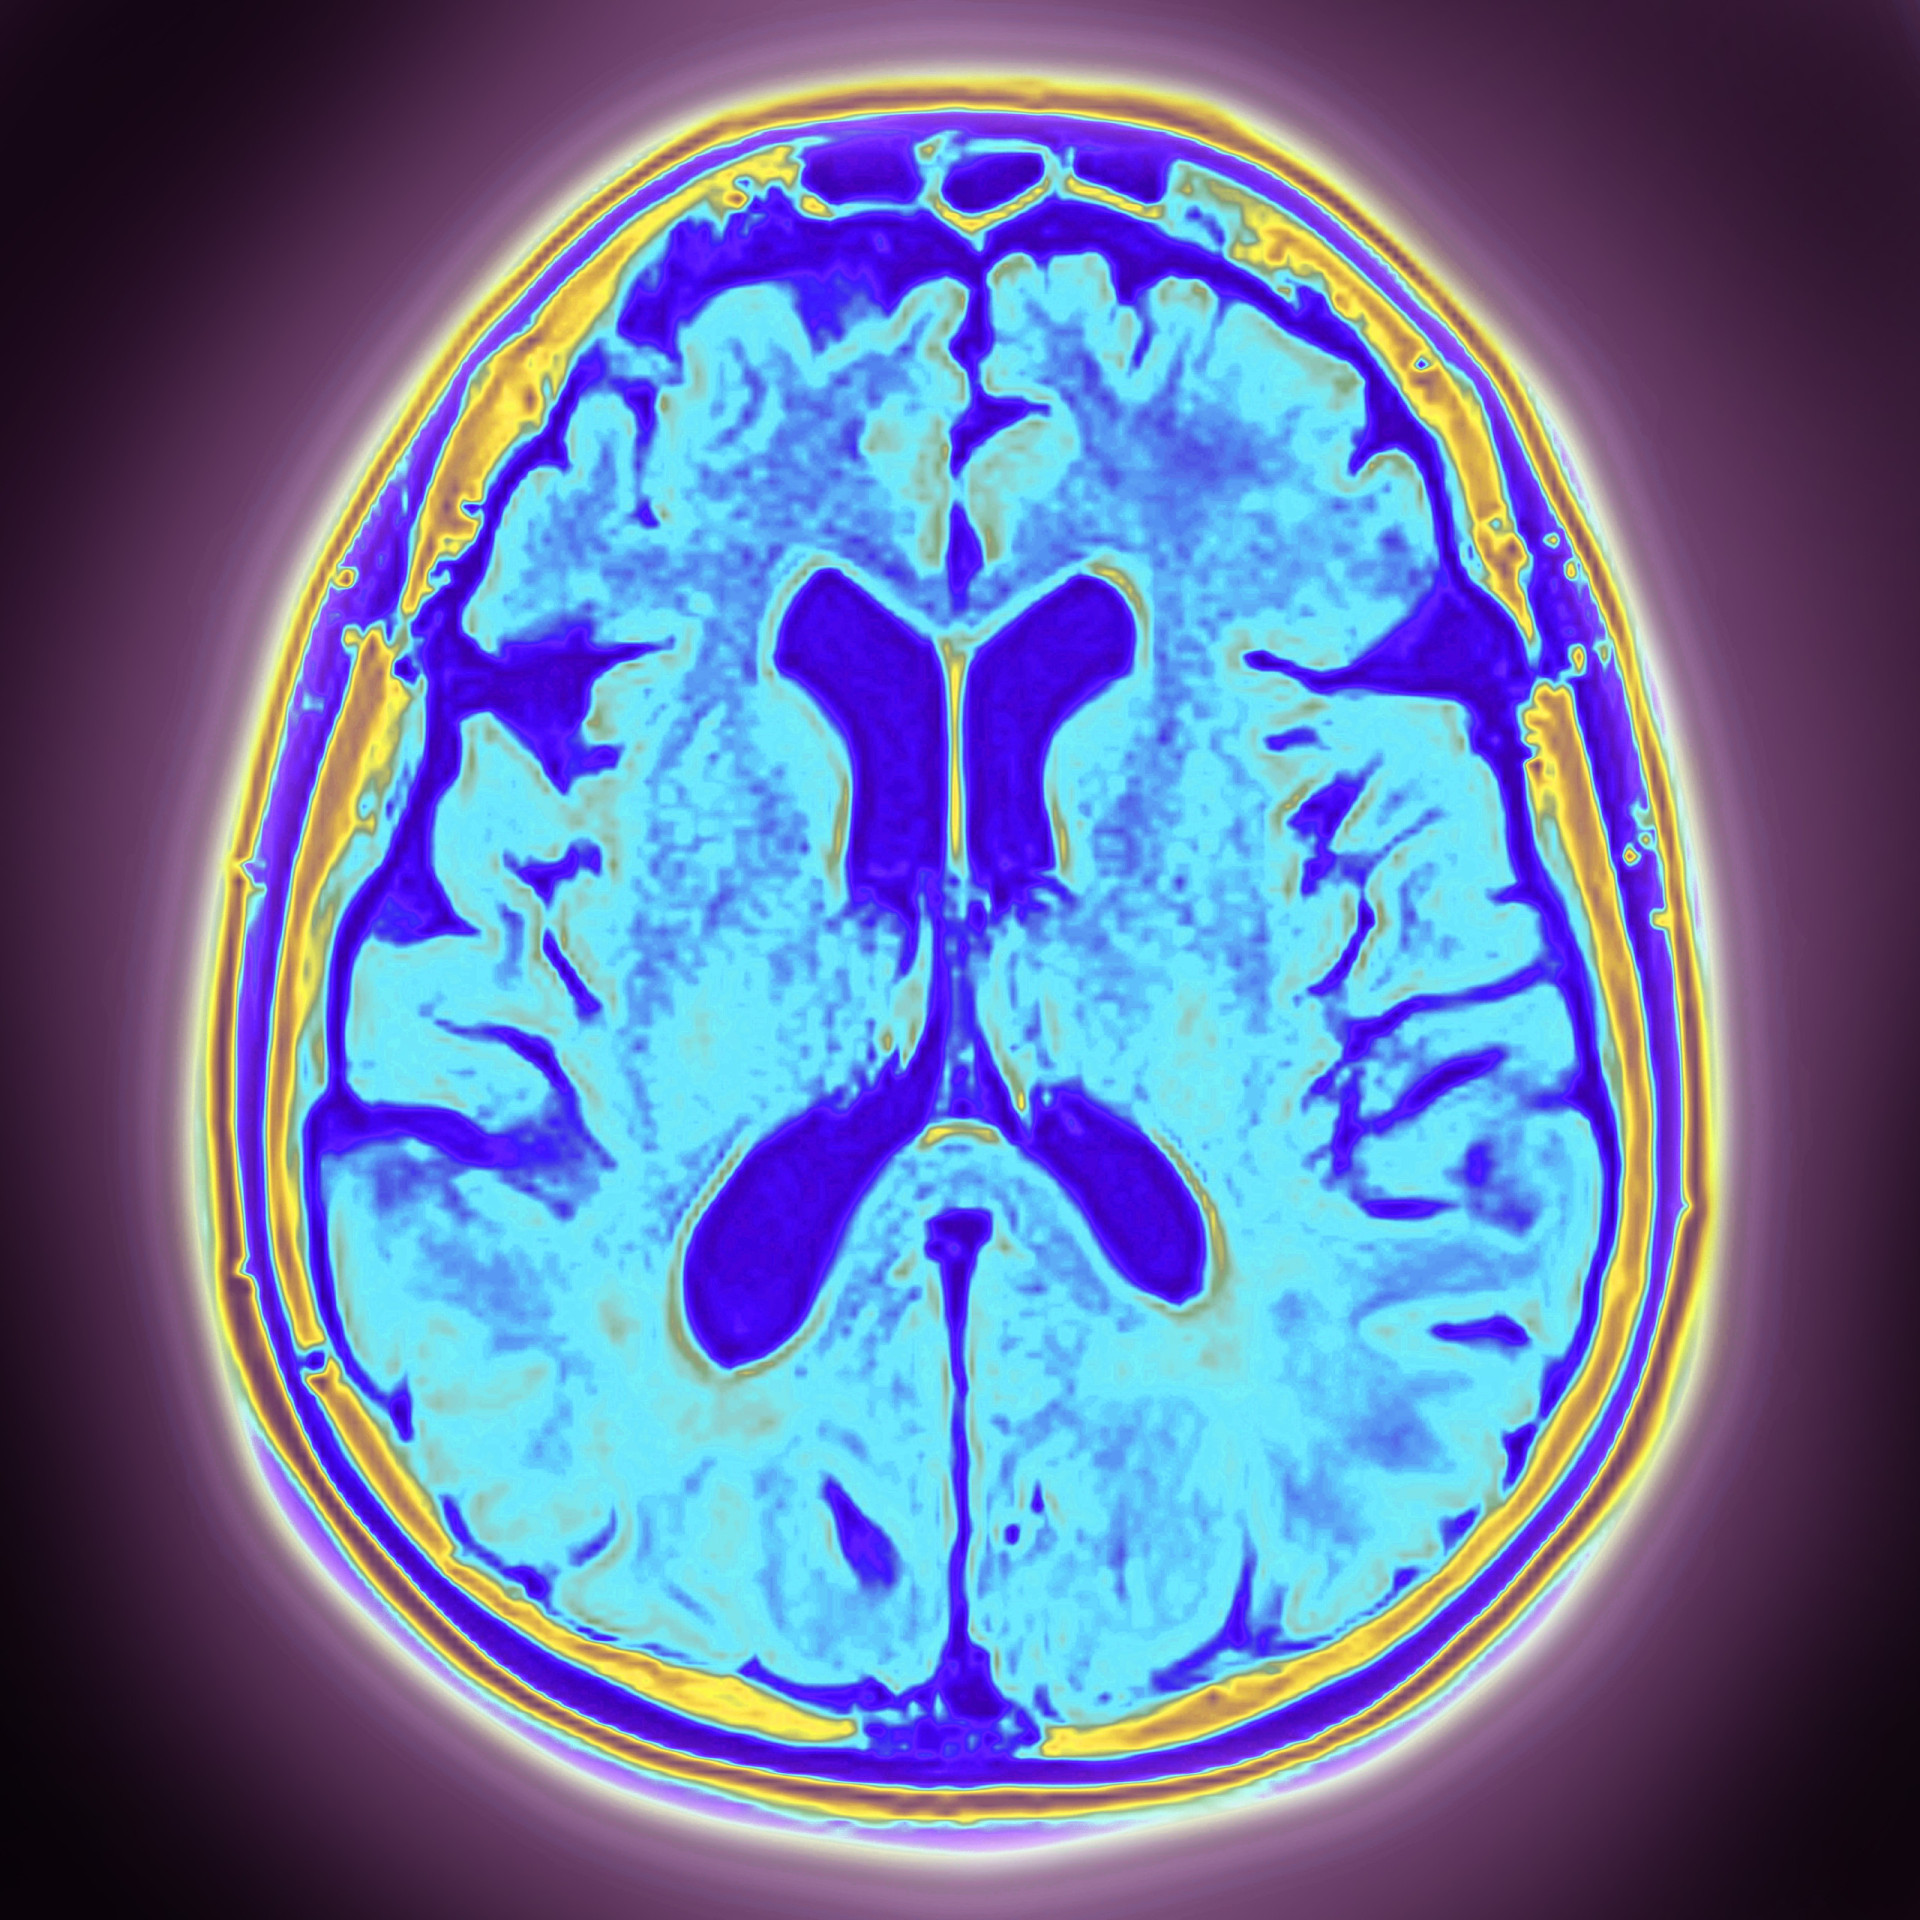

Frontotemporal dementia is an umbrella term for a group of brain disorders caused by progressive nerve cell loss in the brain's frontal and temporal lobes. Unlike Alzheimer's, which typically begins with memory loss, FTD primarily affects personality, behavior, and language. Bruce Willis' experience aligns with the language variant, but understanding all core symptoms is crucial for recognition.